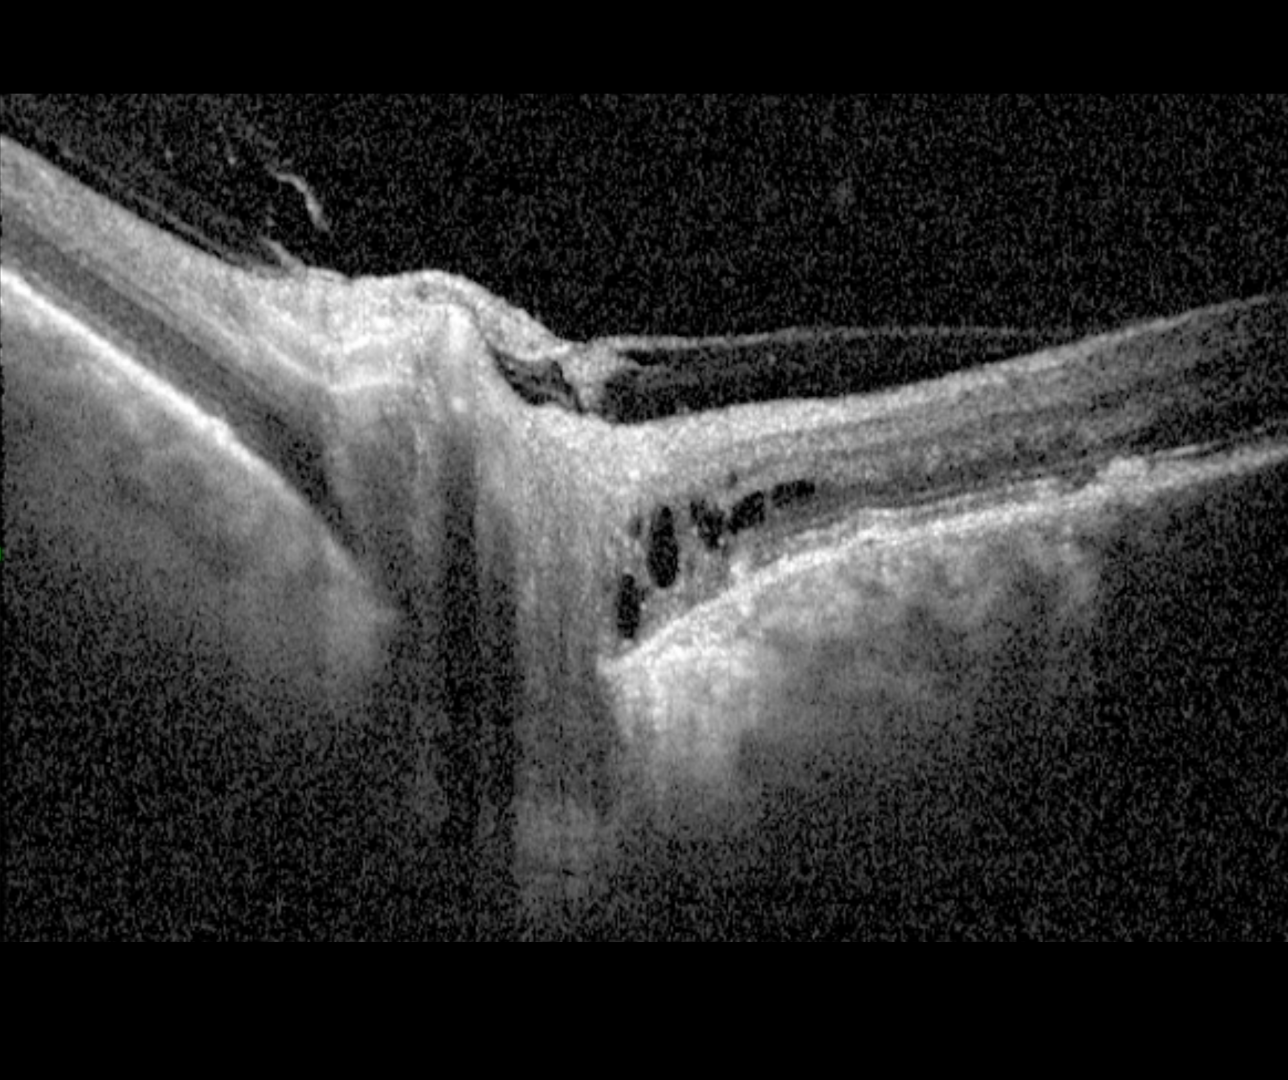

Peripapillary pachychoroid syndrome is an entity under the pachychoroid disease spectrum in which peripapillary choroidal thickening is associated with nasal macular intra and/or subretinal fluid. The optic disc typically has a crowded appearance or occasionally oedematous and RPE mottling and pachyvessels are seen on OCT using enhanced depth imaging.

Xu et al. (2020) found that approximately half of peripapillary pachychoroid syndrome cases have a peripapillary area of cystic fluid within the outer nuclear layer (ONL), located temporal to the disc and distinct from any other areas of intra-retinal fluid.

More infoSpectralis OCT line scans - superior right macula (1) and right optic disc (2)

More infoSpectralis OCT line scans (left optic disc)

More infoSpectralis OCT line scans (left macula)